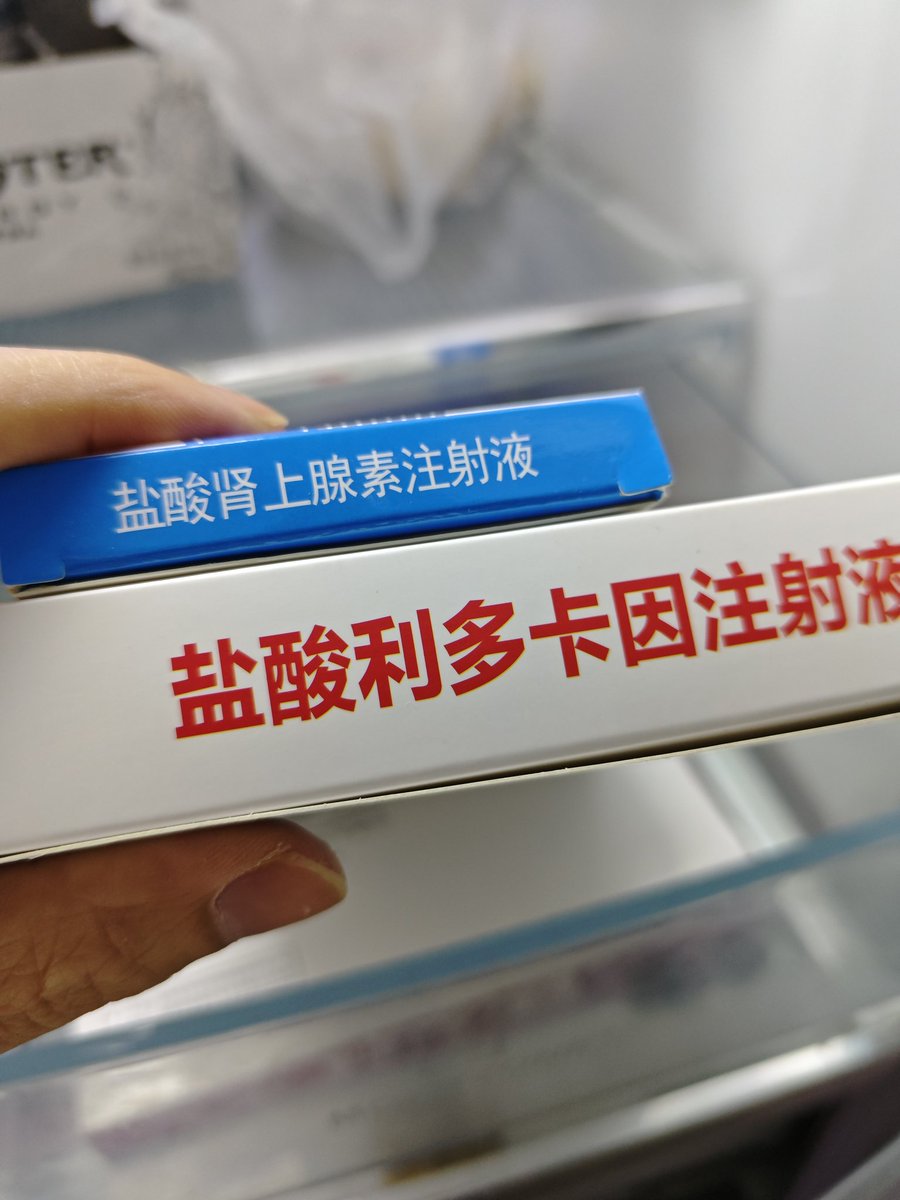

对于药物过量引起的中枢神经系统副作用,有一些不常见或常见的药物来控制症状。

评论区欢迎补充 https://t.co/7S4tGVDEM5